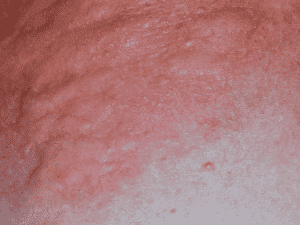

Hives (urticaria) is a very common and often temporary skin condition that can appear in both adults and children. It can be acute, which means it appears once; or chronic, which means it is recurring multiple times over 6 weeks or more. The cause of hives is the immune system releasing histamine into the skin, resulting in redness, swelling and itching. It may recede quickly—within minutes to hours—or take up to 24 hours before it disappears altogether. Nevertheless, hives are rarely serious in nature and easily treated.

Hives usually appears as a series of raised, red bumps that come up within minutes and can resemble mosquito bites or nettle rash. It can be limited to a small area or span large expanses of the body. Sometimes there is swelling of the face and eyes (angio-oedema). The rash often resolves over a period of an hour or two, but might last as long as 24 to 36 hours. There are a number of different types of Hives: